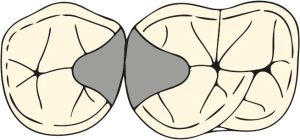

The occlusal rest seat is triangular with the base at the marginal edge and the apex at the center of the tooth. The outer edges of the rest seat and especially the apex of the triangle should be rounded. The ideal width for the occlusal rest seat is approximately half the distance between the buccal and lingual cusp tips for premolars and slightly less for molars (Figure 10-31).

Embrasure rest seat

The embrasure rest seat extends from the mesial fossa of one tooth to the distal fossa of the adjacent tooth, encompassing the occlusal embrasures of two adjacent teeth (Figure 10-39). Preparing this rest seat is more challenging. To provide space for the retentive and reciprocal clasp arms, the rest seat preparations are enlarged both buccally and lingually. The embrasure clasp that will be placed on this seat will be thin and break in the vestibule and lingual marginal ridge of the teeth if these areas are not adequately prepared. It may also cause occlusal interference with the opposing arch.